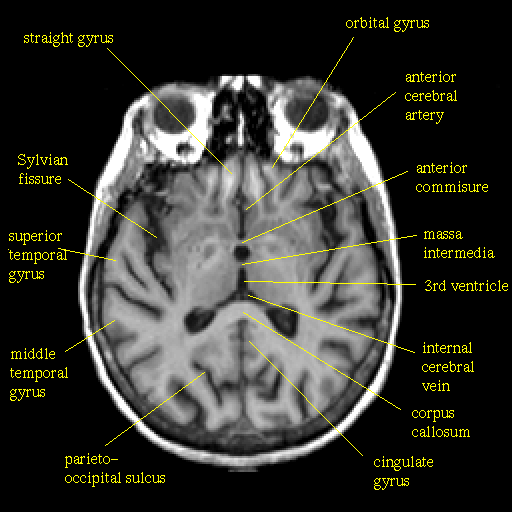

T1-weighted structural MR: Slice 27

Slice 27